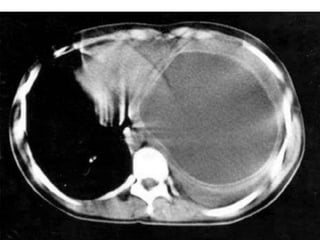

• Stade IV:

• images hydroaériques d’aspect variable

- Nénuphar +++ ( ds 10% rupture)

Aspect de membrane flottante surnageant la surface ou immergée

dans le liquide

- Opacités avec image de niveau hydroaérique

rectiligne

- Image en double arc d’Ivassinevitch, réalisée par la

superposition de deux épanchements gazeux l’un intra-kystique et

l’autre intra-adventiciel séparés par la membrane flétrie de

l’hydatidose